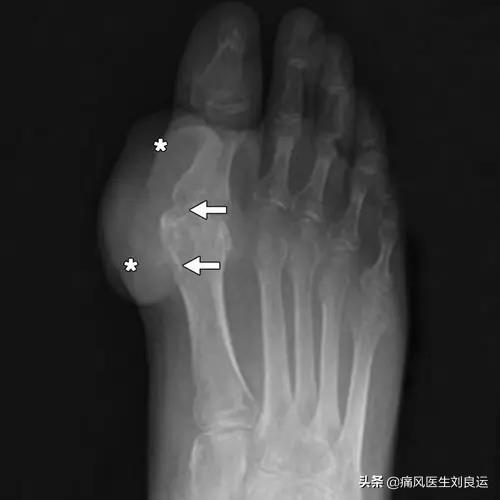

第2段階は、例えば超音波検査で「ダブルトラックサイン」を検出したり、画像検査を行うことである。デュアルエナジーCTで尿酸塩沈着が見つかるなど、そしてX線検査で軟部組織の腫脹、軟骨辺縁の破壊、関節面の不整が認められる。!

- (10) 左右非対称の関節内腫脹(X線で確認)

- (11) 骨びらんを伴わない骨皮質下嚢胞(X線で確認)